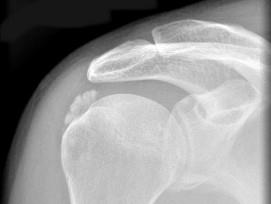

问题 男,52岁,肩痛四月余,手臂旋转时疼痛加剧,请结合影像图像选择最可能的诊断 ( )

选项 A、骨囊肿 B、骨脓肿 C、骨结核 D、冈上肌腱钙化 E、软骨瘤

答案 D